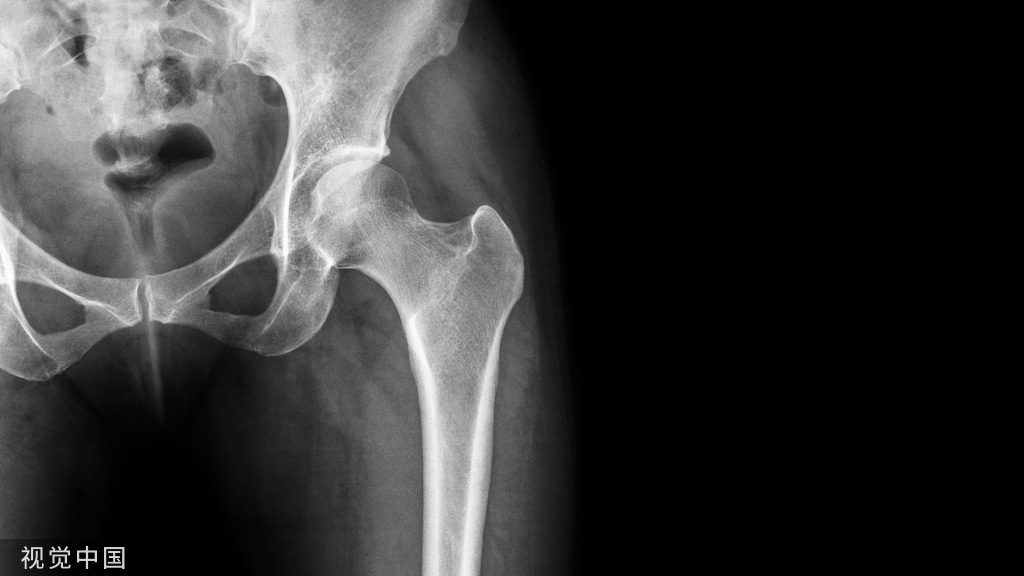

研究乳牙根管形态的方法有组织切片、镍钛锉探查、X线片、透明牙技术等,但均存在不足之处:组织切片样本量少,不够直观,来源困难;镍钛锉探查及X线平片具有不确定性,容易遗漏根管。

1、术前拍X片,了解尖周病变和牙根吸收情况。牙根吸收已达1/3以上者,难获良好的疗效。

2、预备根管时应测根管长度以防器械超出根尖孔,以免将感染物质推出根尖孔或损伤恒牙胚。

5、术后应拍X片观察根充情况,分类:

①适充填:恰填或距根<1mm;

②欠充填:糊剂未充满根管,距根尖孔>1mm;

③超充填:糊剂超出根尖孔。

3、X线显示病变消失或原有阴影缩小,超出糊剂已完全吸收,恒牙胚无异常发育。

2、X线显示:牙根病理性吸收或病变扩大等。